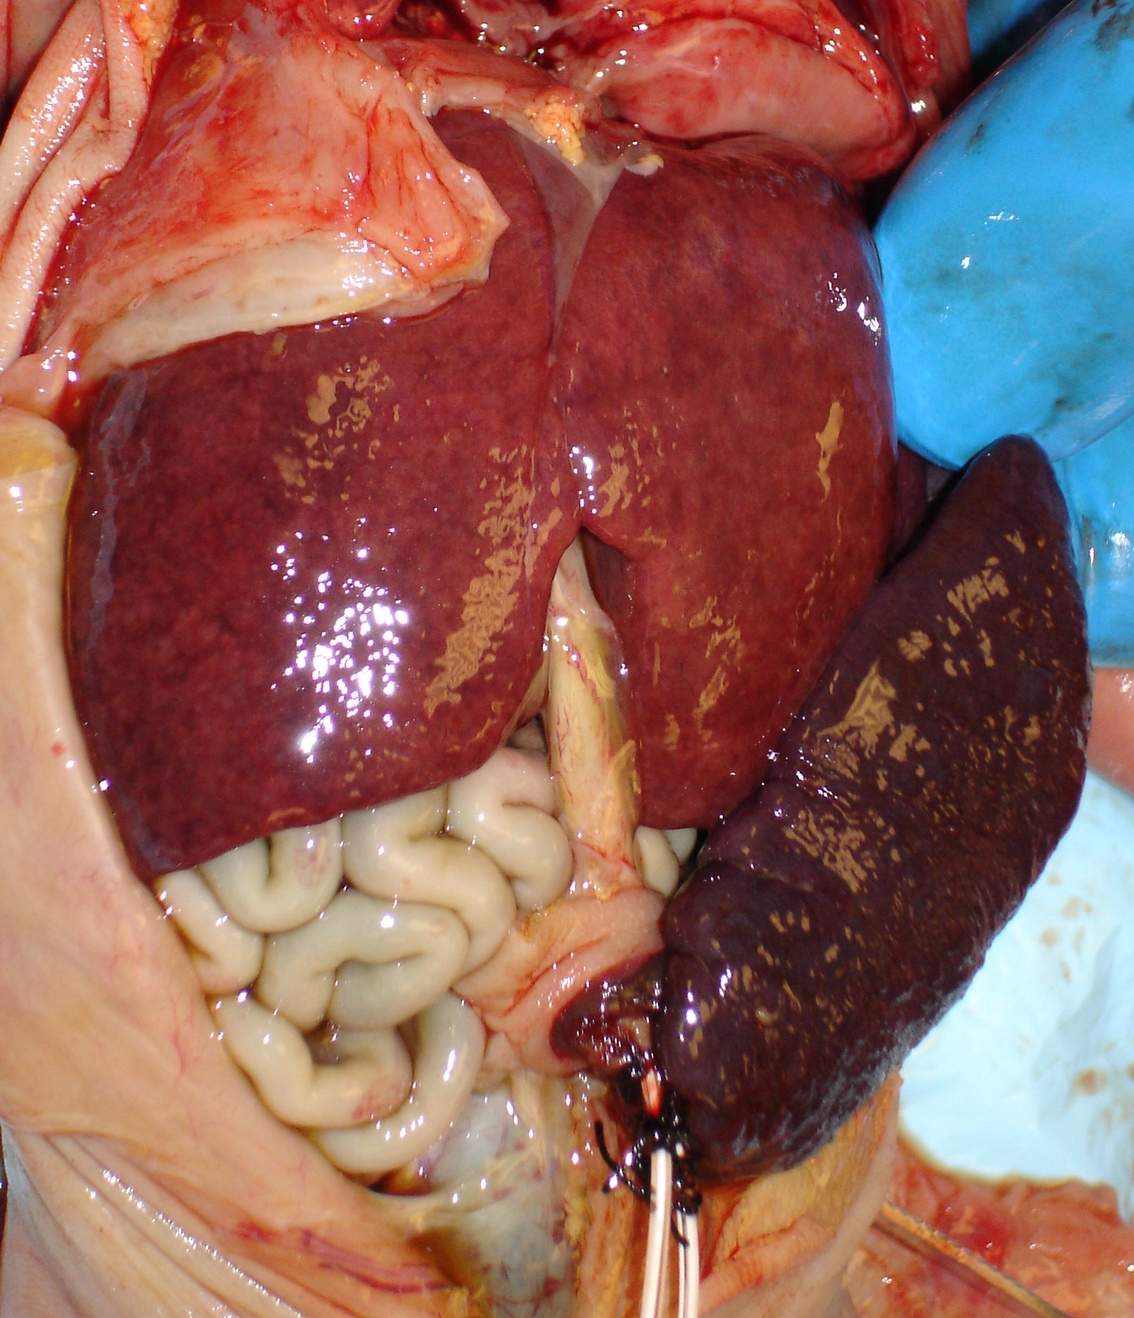

The spleen is easily located along the left edge of the stomach. Looking at the organ from the posterior, the tail of the pancreas reaches to it. By lifting the tail, pancreas can easily be dissected free toward the duodenum. The spleen is occasionally malformed, for example trisomy 13, or demonstrates small splenules at the splenic periphery. In heterotaxy syndromes, there may be asplenia or polysplenia, and the multiple spleens are often on the right side of the body1 (Fig 1).

Fig 1a: The stomach is on the right side of the abdomen, and the arrows point to multiple spleens in this infant with polysplenia syndrome with bilateral left lungs and cardiac malformation. The infant was 20 weeks of gestation with prolonged retention.

Fig 2: The abdomen shows hepato-splenomegaly in a 26 weeks of gestation infant with congenital CMV infection, who survived 24 hours.